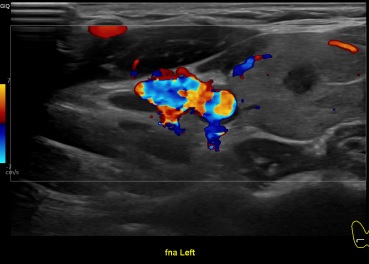

상기환자 외부검사이상소견으로 정밀검사위해 내원하신 30대 후반 여성분으로 갑상선 초음파 시행후 의심스러운 갑상선 좌엽 결절 세포검사 진행후 갑상선암으로 진단되었습니다